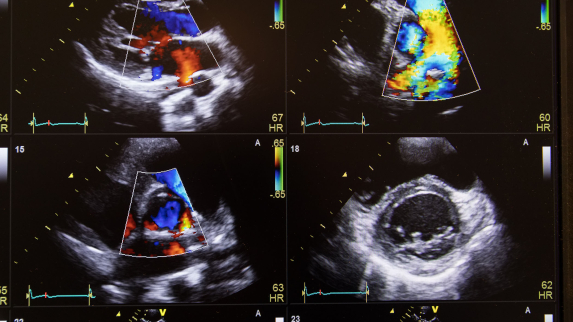

Pocket Ultrasound Reduces Hospital Stays for Patients with Shortness of Breath.

When hospitalized patients struggle to breathe, doctors typically reach for their stethoscopes, but results from a Rutgers and RWJBarnabas Health clinical study in JAMA Network Open suggest they should diagnose the problem with portable ultrasounds instead....